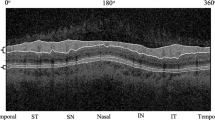

OCT examination was performed by an experienced technician using a spectral-domain OCT (3D OCT-1, Topcon, Tokyo, Japan). Topcon 3D OCT-1 is a non-contact SD-OCT system that performs a fully automated “alignment, focus, and capture” procedure by capturing 50,000 axial scans per second [19]. Herein, the “3D wide scan mode” was selected to provide a 12 mm × 9 mm scan measurement and topographical maps of the optic nerve and macula (Fig. 1a). The mode also featured an automatic segmentation of RNFL, total retina, GCIPL, and GCC (Fig. 1b–d, e).

The 12 × 9 mm scan region (A). Measurement areas for cpRNFL circle (B). Macula ETDRS grid (C), macula 6 circle for GCIPL, and GCC (D) overlaid with example projected images. Full retinal thickness (distance between the red and green boundaries); ganglion cell + inner plexiform layers (distance between the yellow and blue boundaries); ganglion cell complex (distance between the red and blue boundaries, vitreal to inner nuclear layer) (E). All the images were set with the right eye orientation.

The macula full retinal thickness (FRT) was defined as the distance between the inner limiting membrane (ILM) and the outer segments/retinal pigment epithelium junction boundary. It was divided into nine quadrants based on the ETDRS map (Fig. 1c). The diameters of the three circles on the ETDRS map are 1, 3, and 6 mm. In the same line, GCIPL thickness was defined as the distance from the interface between the NFL and ganglion cell layer (GCL) to the interface between the inner plexiform layer (IPL) and inner nuclear layer (INL). GCC was defined as the distance between the internal limiting membrane and the interface between the IPL and INL. It was the sum of RNFL and GCIPL (Fig. 1e). The temporal-superior-nasal-inferior-temporal (TSNIT) circle with a diameter of 3.4 mm was placed automatically at the optic disc center to obtain the optic nerve head parameters. The thickness of cpRNFL was assessed over 4 quadrants and 12 clock-hour sectors around the TSNIT circle (Fig. 1b). The optic disc contour was automatically detected. However, the disc area, cup area, rim area, cup/disc (C/D) vertical diameter, C/D area, cup volume, and rim volume were measured.

A Thickness distribution maps of macular layers. Topographic distributions of macular FRT, GCIPL, and GCC thickness in different sectors are shown through the picture. B 12 clock-wised sections of cpRNFL thickness distribution. The mean ± SD values (lm) are presented. S superior, I inferior, N nasal, T temporal.

RNFL thickness, distribution, and optic disc parameters

The overall cpRNFL thickness and distribution are shown in Supplementary Table 1. The average cpRNFL thickness was 112.86 ± 11.94 μm. The thickest area was the inferior region (146.99 ± 19.13 μm), followed by the superior (144.90 ± 17.60 μm), the temporal (79.99 ± 12.88 μm), and the nasal quadrants (79.51 ± 16.00 μm). The thickness and distribution of the 12 individual sections (each section was 30°, corresponding to a clock-wised hour) were also different. The thickest region was in the 6 o’clock section (162.11 ± 28.15 μm), while the thinnest was in the 3 o’clock section (61.56 ± 14.79 μm). However, the cpRNFL thickness of the 12 sections was more discrete than that of the 4 regions (Inferior, superior, temporal, and nasal) (Supplementary Table 2 and Fig. 2b).